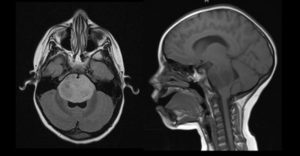

Guidance for assessing treatment response in pediatric brain tumors

Assessing patients’ response to cancer therapy can be challenging, especially in neuro-oncology. Generally, we assess treatment response by a change in tumor size on MRI scan. However, with brain tumors, changes on MRI scan can be difficult to interpret. A decrease in tumor size may indicate treatment is having an effect; however, a drug can ... Read More about Guidance for assessing treatment response in pediatric brain tumors